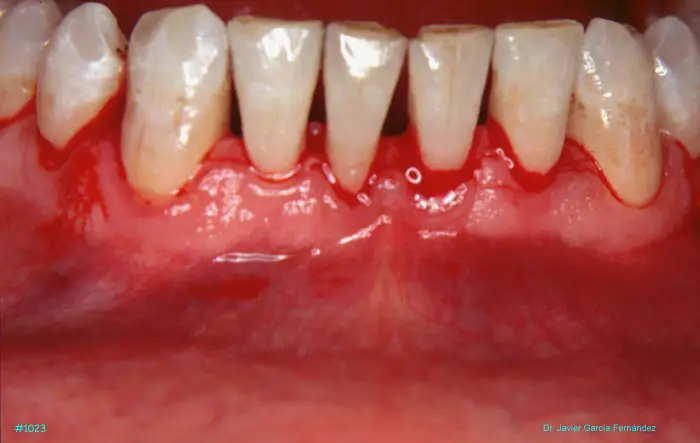

Atlas of Surgical Techniques in Periodontics. Chapter III. Atlas de Técnicas Quirúrgicas en Periodoncia